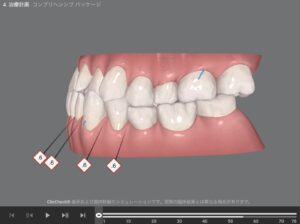

🔶初診時🔶

正面

右

左

軽い受け口の せったん咬合を気にして

マウスピース矯正希望で来院